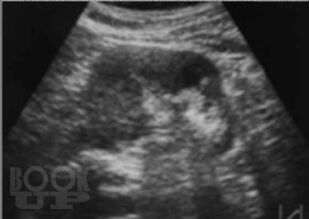

Настоящая монография предназначена для врачей – лучевых диагностов, урологов, хирургов, терапевтов, семейных врачей, а также студентов медицинских вузов, и посвящена применению лучевых методов исследования в диагностике различных форм острого гнойного пиелонефрита.

В монографии детально показана разнообразная лучевая семиотика при апостематозном пиелонефрите, карбункуле и абсцессе почки, а также представлены различные современные методы лечения с динамикой воспалительных изменений в паренхиме почки.